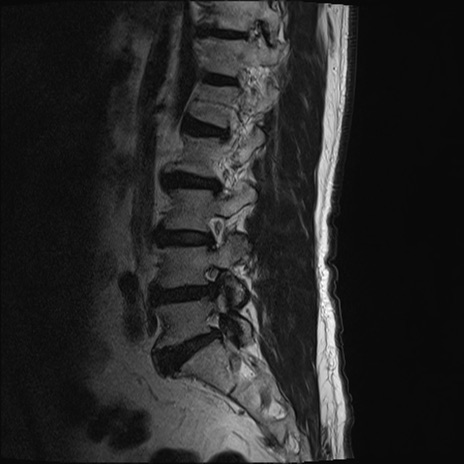

【整形】TIPS症例2 腰椎MRI T2WI(矢状断像)

【症例】70歳代男性

【主訴】左下肢痛

【現病歴】2週間前くらいから腰痛、左下肢痛あり。左臀部から大腿、下腿外側のしびれが常時ある。歩行とともに同部位の痛みあり。

【身体所見】Lasegue70-/60+、Bragard-/±、PTR ±/±、ATR -/-、IP 5/5、TA 5/4、TS 5/5、EHL 右第1足趾なし/3、FHL 5/5、hypersthesia(-)、足背動脈触知良好

異常所見と診断は?